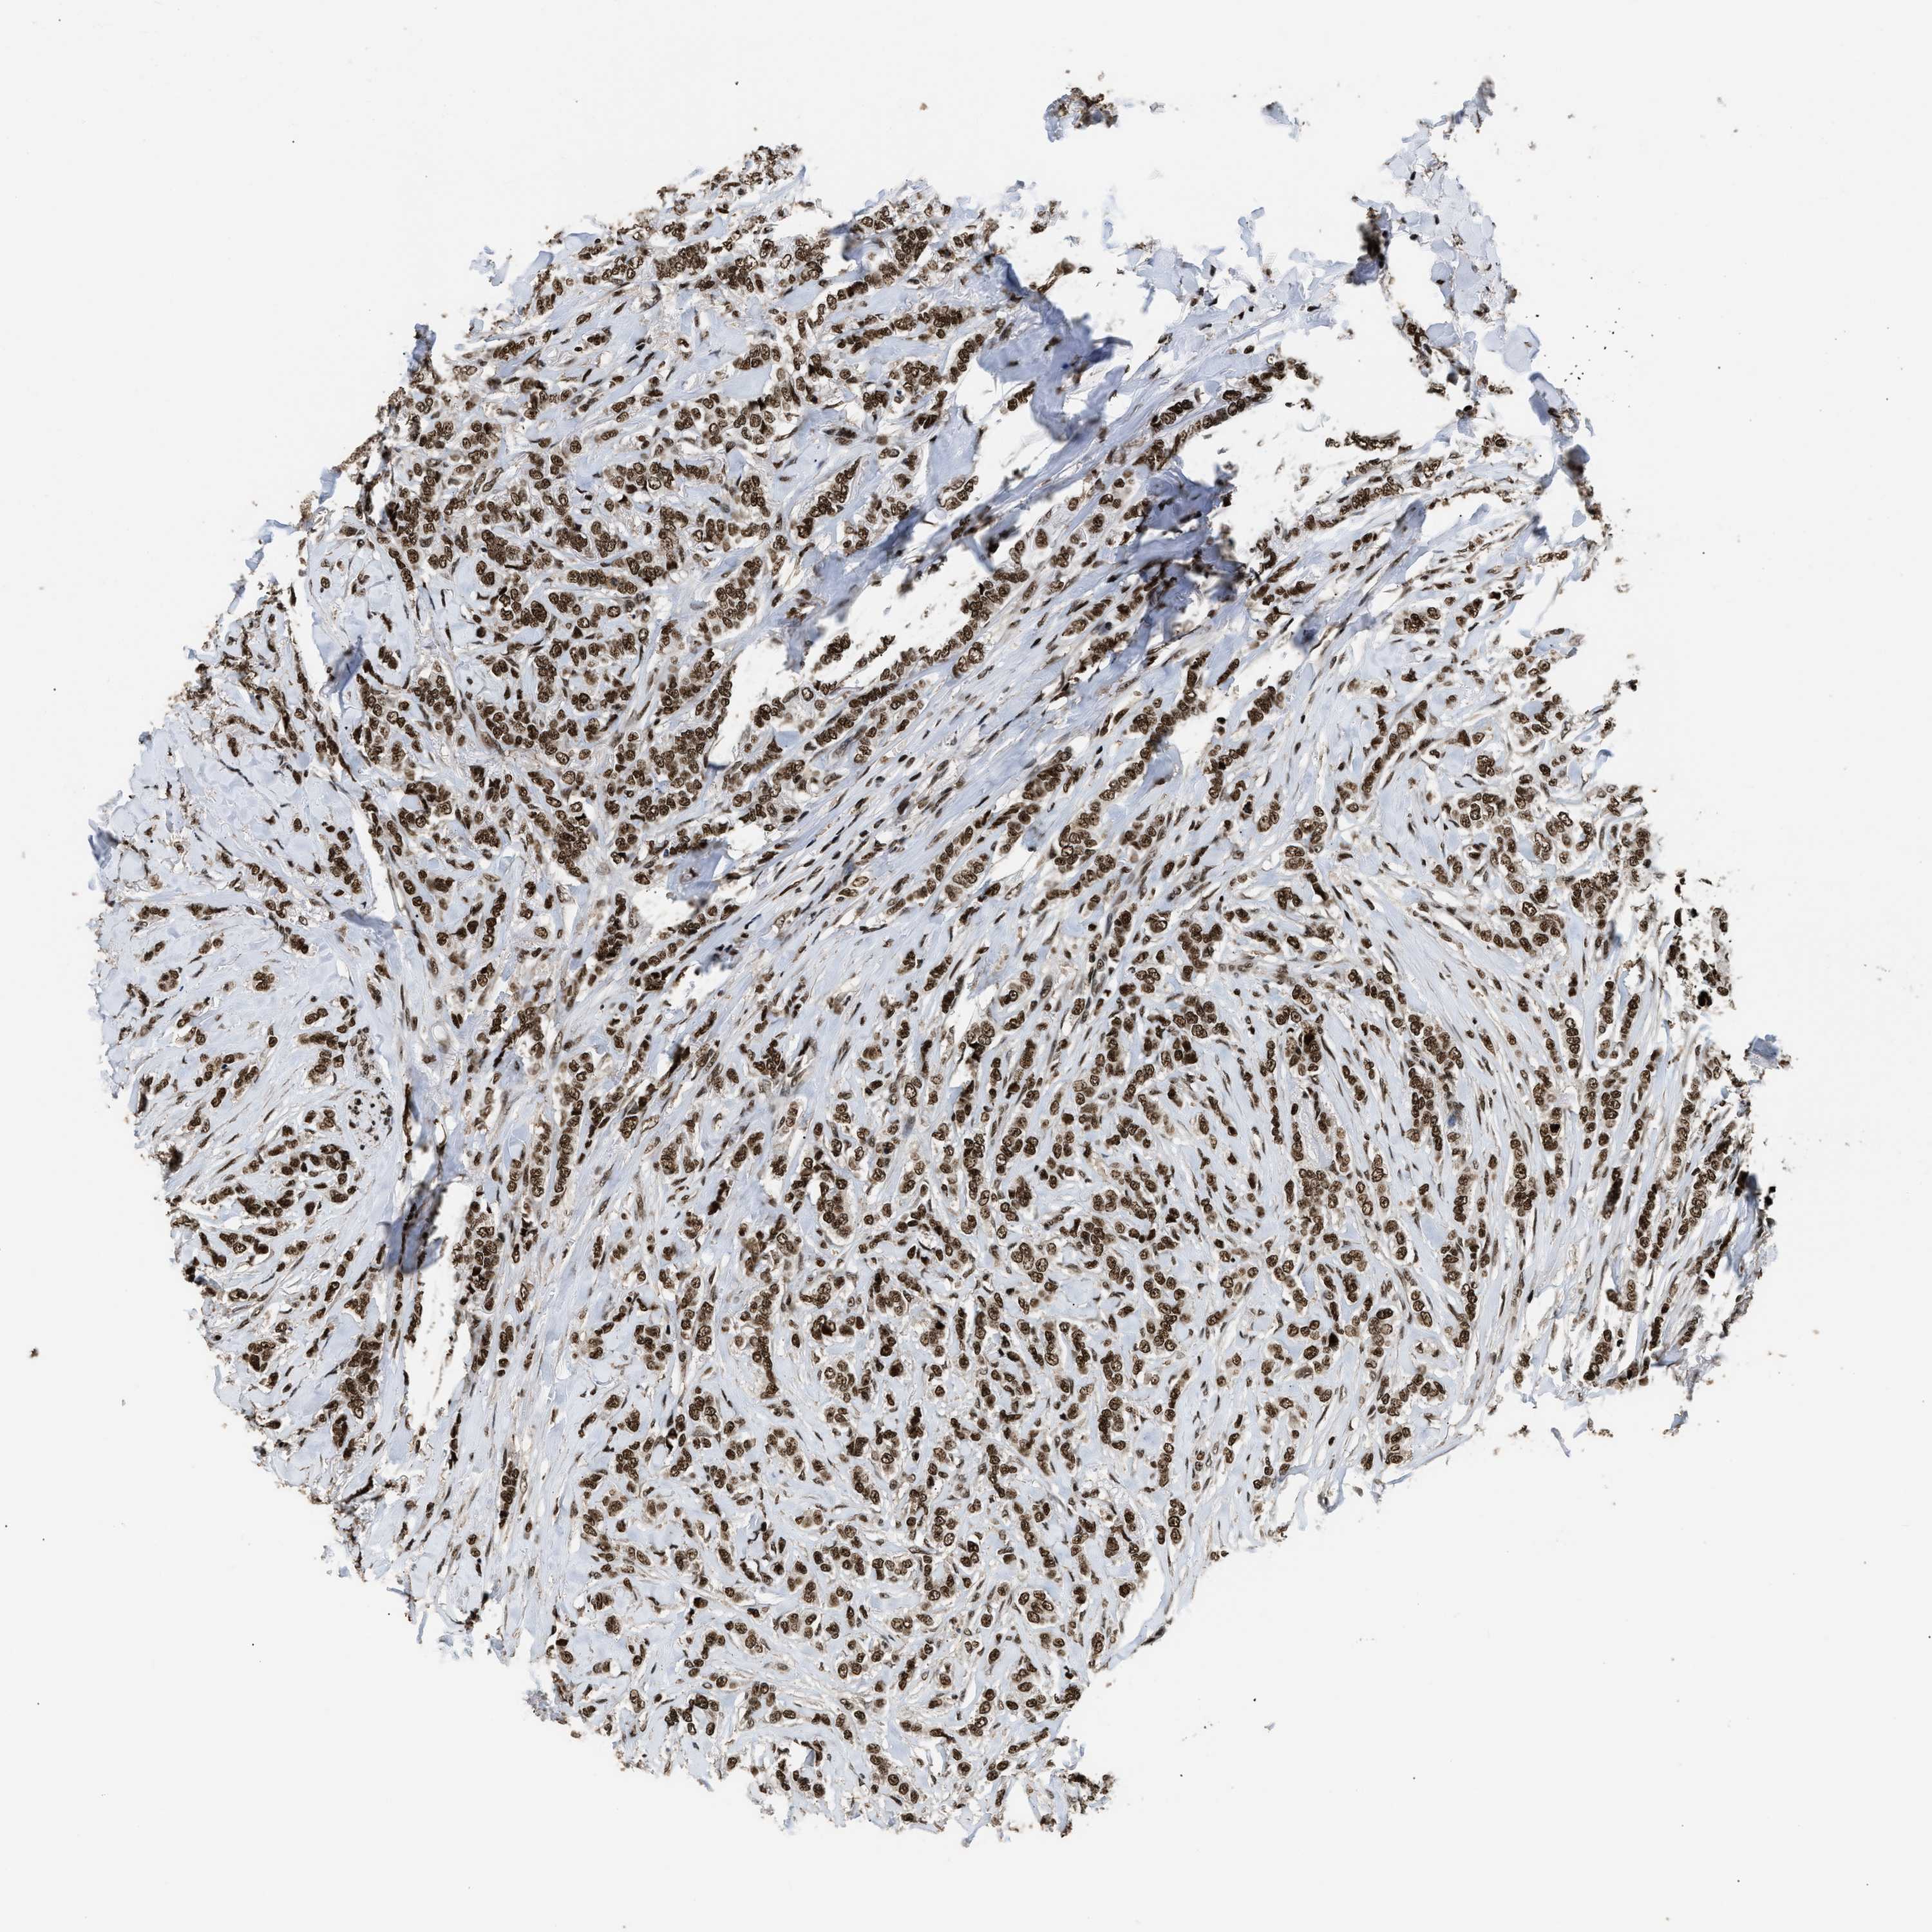

CANCER BREAST CANCER Show tissue menu

BRCA TCGA BRCA VALIDATION PROTEIN EXPRESSION

ANTIBODIES

AND

VALIDATION